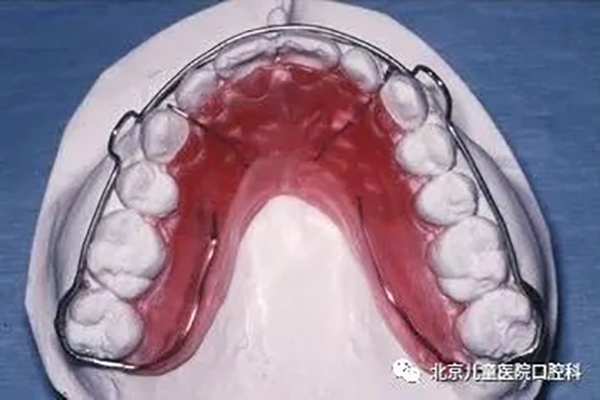

1、Hawley保持器:矫治结束后有利于深咬合的控制,并允许后牙少量调整达到更紧密的咬合关系。